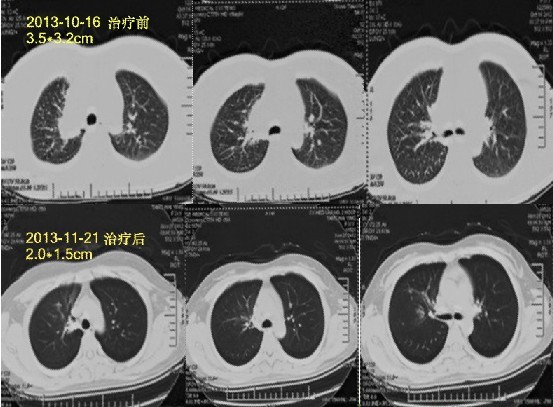

患者姓名:马小姐,33岁,确诊为肺癌

简要病史:经过朋友推荐来到广州中医药大学金沙洲医院肿瘤综合诊疗中心医院进行检查,检查后诊断右肺上叶肺癌,纵膈淋巴结转移,腰椎转移,心包积液,多发骨转移,多发脑转移,手术风险很大,朋友、家人都着急了,患者自己也慌了,听从专家的安排,进行多学科综合治疗治疗:WB-1无创全身热疗系统+基因治疗,两个疗程之后,患者健康恢复显著,半个月患者出院。